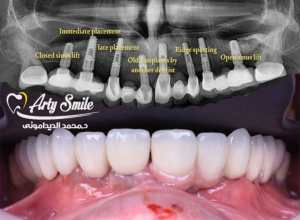

وهناك أكثر من طريقة للزراعة منها الفورية والكلاسيكية

الزراعة الفورية وهي أن تتم زراعة الأسنان بعد خلع السن أو الضرس المصاب فوراً وقد زادت هذه الطريقة شيوعاً نظراً لنجاحاتها إذا توفرت الشرط اللازمة وكذلك سرعتها وعدم الانتظار لفترة التئام أربع لستة أشهر ومن ثم وضع الزرعات

الزرعات الكلاسيكية وهي وضع الزرعات بعد تمام إلتئام العظام لفترة أكثر من ستة أشهر أو أن الخلع مر عليه فترة طويلة ومن ثم يتم التشخيصات السابقة لإتمام عملية الزراعة

الزراعة الفورية كما ذكرنا لاحقا وهو أن يتم استبدال السن التالف أو المكسور بزراعة عقب الخلع مباشرة ويمثل هذا النوع من النجاحات المرتفعة جدا في تماثل الأنسجة والتآمها حول الزرعات وذلك إذا توفرت الشروط اللازمة لذلك

الزراعة الكلاسيكية أو المتأخرة وتكون بعد الخلغ بفترة أكثر من 4 أشهر بحيث يكون تم التآم وتشكل عظام الفك بشكل ثابت ومن ثم يتم التخطيط لزراعة الأسنان